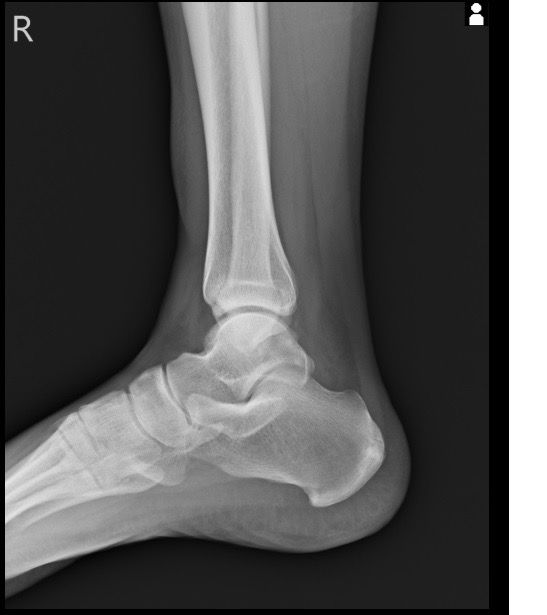

복숭아뼈 골절이 맞는 걸까요 엑스레이 사진 올립니다

3월1일 다리 접질린 후 약간의 통증과 심한 붓기 멍으로 3월7일 병원 방문. 정형와과에서 엑스레이 초음파 검사 후 골절진단 받았네요 그뒤 반깁스란 목발 받고 3일 후 다시 반깁스 하고 왔습니다 사진상에는 뼈가 떨어진 부분이 없는데 미세골절이라 그럴까요

• 3번 째 사진

사진상으로는 정확한 상태를 확인하기 어려우나 병원에서 골절 진단을 받으셨다면 골절일 가능성이 높고 엑스레이에서 뼈가 떨어진 부분이 보이지 않는다면 미세골절일 가능성이 높습니다.

미세골절 같은 경우 엑스레이상으로는 뚜렷하게 보이지 않기 때문에 검사 결과로 진단 할 수 있습니다.

엑스레이에서 뼈가 떨어진 부분이 보이지 않는다면 미세골절일 수 있습니다. 미세골절은 엑스레이에서 뚜렷하게 보이지 않지만 증상과 검사 결과로 진단할 수 있습니다.

네, 골절에는 반드시 뼈가 떨어지는 변화가 일어나는 것은 아닌데요, 미세골절의 경우에는 큰 변화가 발생하지는 않습니다.